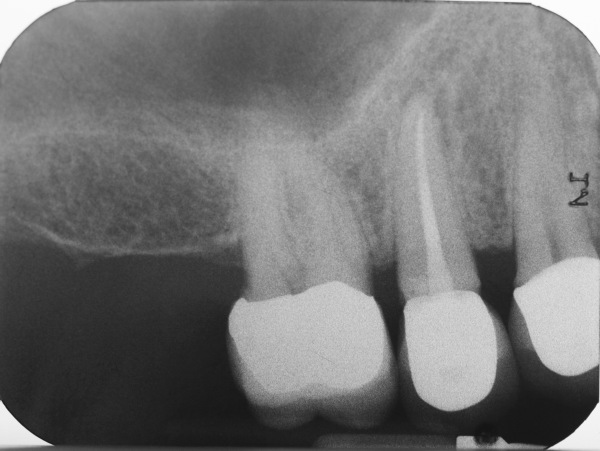

Sicherlich eignet sich nicht jede Wurzelbehandlung für ein single-visit-treatment. Zum einen läßt der ein oder andere Fall keine andere Wahl, da beispielsweise der Wurzelkanal in Vorbereitung der Wurzelfüllung nicht zu trocknen ist. Zum anderen sind bei Behandlungsumfänge jenseits der 90 Minuten für manch einen Patienten kaum auszuhalten. Die Behandlungs muss also zweigeteilt werden. Kleine Backenzähne wie im folgenden einer dargestellt oder Frontzähne sind fast prädestiniert für einzeitige Behandlungen. Der Fall dieses kleinen Backenzahnes mit einer lateralen Aufhellung ist ein Beispiel dafür. Der große schwarze Fleck rechts neben der Wurzel, ein apikales Granulom oder Entzündungsherd, war zur Nachkorntrolle so gut wie vollständig ausgeheilt.